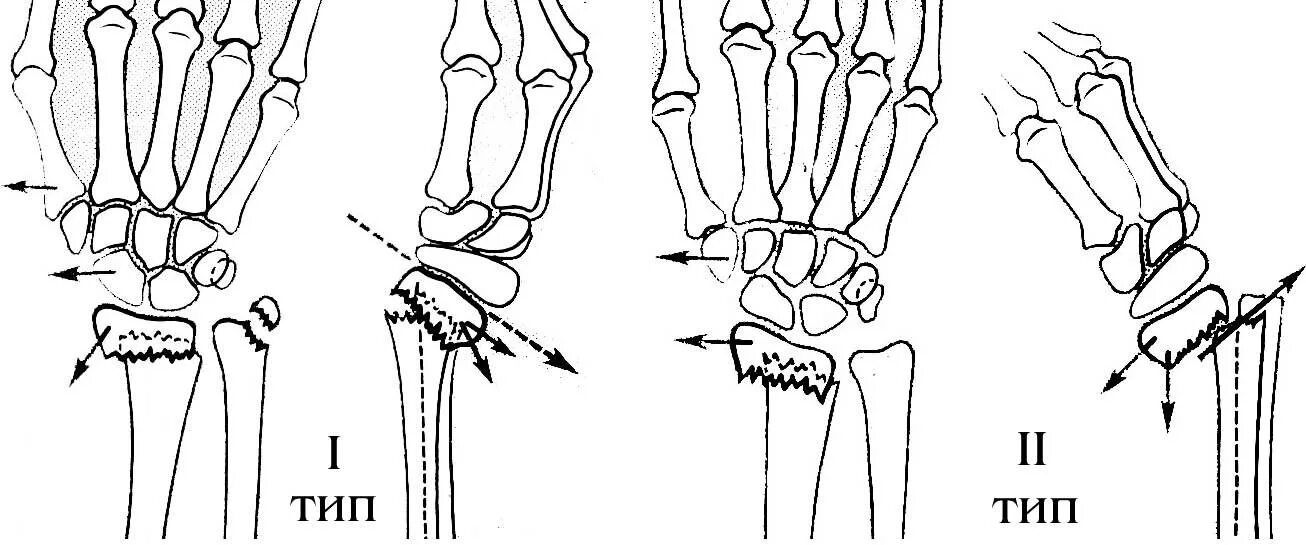

Перелом смита